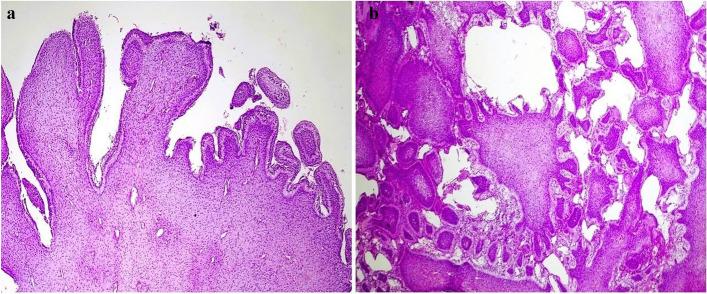

伴有牙源性角化囊肿的原发性牙源性肿瘤的组织病理学谱:世界上 1 例报道病例,并提出了“更新的诊断标准”。

Histopathological spectrum of primordial odontogenic tumor with co-existing dentigerous cyst: 1 reported case of the world with a proposed 'updated diagnostic criteria'.

POT is a relatively newly described benign odontogenic tumor with very few cases registered to date. We present the 1st case of Primordial odontogenic tumor (POT) from Sub-Saharan Africa with unique clinicopathological features; also, this is the first case to report POT's existence as a Hybrid Odontogenic lesion (HOL), with a pertinent review of the literature.

CASE PRESENTATION

This was a 17-year-old patient who presented with slow-growing, painless posterior mandibular swelling. The imaging revealed a well-defined, unilocular, expansile, lytic lesion with internal calcific foci surrounding an impacted #36, indicating a calcifying odontogenic cyst. The incisional biopsy revealed the presence of POT. The tumor was excised along with the involved tooth.